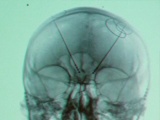

Manchen depressiven Patienten kann mit den besten Medikamenten oder Psychotherapie nicht geholfen werden. Sie gelten als therapieresistent. Jetzt gibt es einen Hoffnungsschimmer und zwar die sogenannte tiefe Hirnstimulation. Erste Ergebnisse aus klinischen Studien sind vielversprechend. Beim Kongress der Deutschen Gesellschaft für Psychiatrie und Psychotherapie, Psychosomatik und Nervenheilkunde (DGPPN) in Berlin (26.-29.11.2014) wurden die Erkenntnisse vorgestellt.

Psychotherapie und Psychopharmaka helfen den meisten psychisch Kranken gut und langfristig bei Depressionen. Aber wie kann denen geholfen werden, die gegen die bekannten Therapien resistent sind? Beim Kongress der Deutschen Gesellschaft für Psychiatrie und Psychotherapie, Psychosomatik und Nervenheilkunde (DGPPN) in Berlin (26.-29.11.2014)  hat Prof. Dr. Thomas Schläpfer, Leiter des DGPPN-Referats "Experimentelle Stimulationsverfahren in der Psychiatrie", vielversprechende Forschungsergebnisse vorgestellt. In dem vorliegenden O-Ton-Paket erklärt er die Wirkweise von tiefer Hirnstimulation.